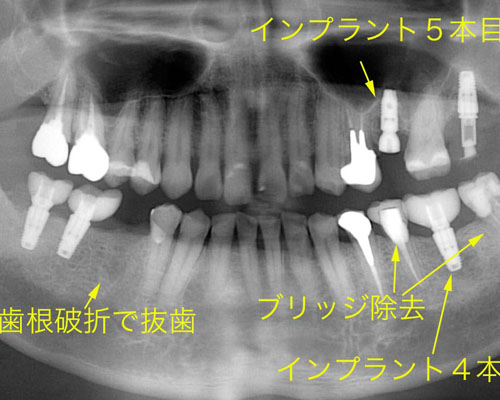

4・5本目のインプラントと左側の歯が割れた

ブリッジの作り直しは無理だったため、インプラントに替えました。左上の奥のインプラントは仮歯まで漕ぎ着けています。そして5本目のインプラントを入れています。ところが、またしても右下が割れました。もう、患者さんは悲鳴をあげています。